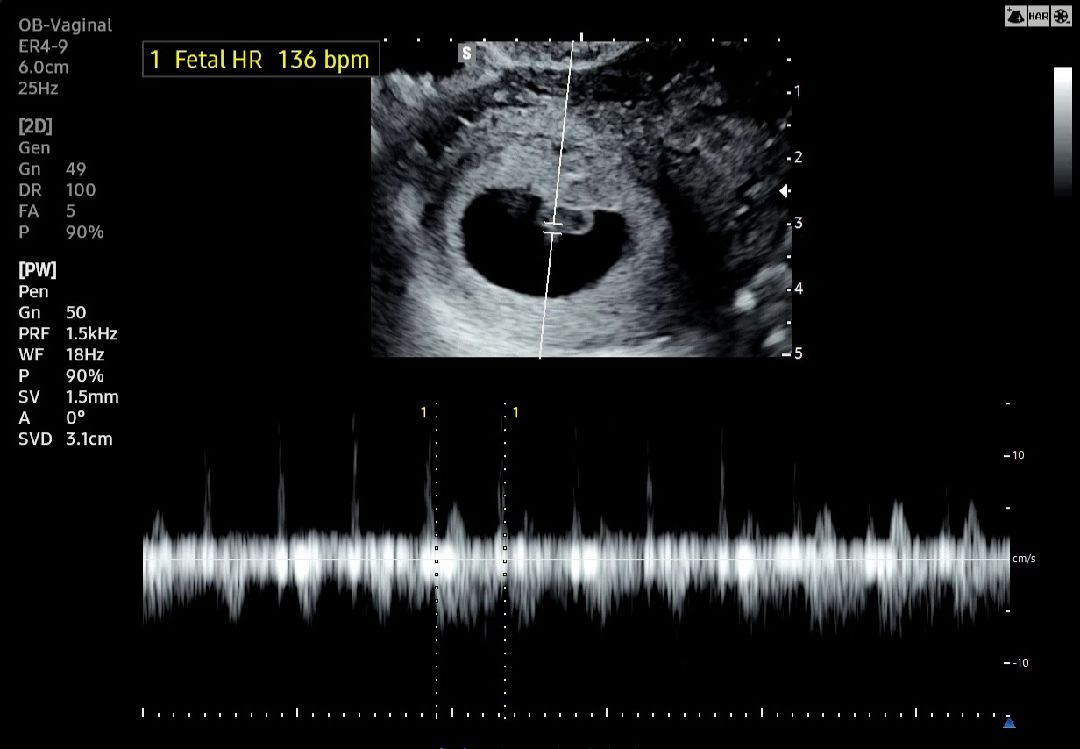

6주 6일차, 드디어 심장소리 듣고 왔어요 🫢❕️

지난 주 초음파에서 다이아몬드링에 아주 작은 빛만 반짝였는데, 일주일 사이에 아기는 0.7cm로 크고, 처음으로 심장소리도 들었어요! 136bpm으로 정상, 난황크기도 정상이라고 해서 안심되는 하루랍니다 🥹🙏🏻 직업 상 몸을 많이 쓰는 직업이라 피고임 걱정했는데, 다행히 주변에 피고임도 없고 깨끗하다고 해요! 건강하게만 자라다오 ~~ 👼🏻🩷💙